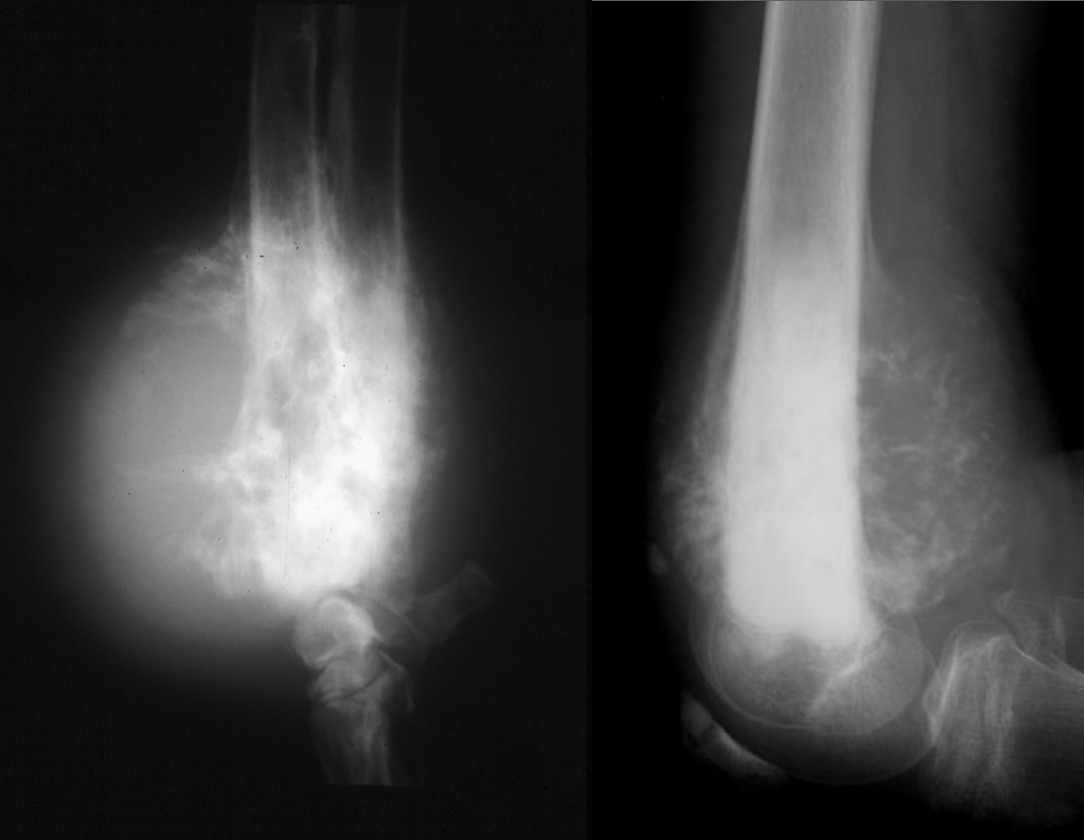

What is shown in these radiographs?

amorphous periosteal reaction

What are the characteristics of amorphous periosteal reaction?

-bone is formed in a disorganized manner

-process may destroy spicules of bone as they are formed

-most aggressive; typically neoplastic